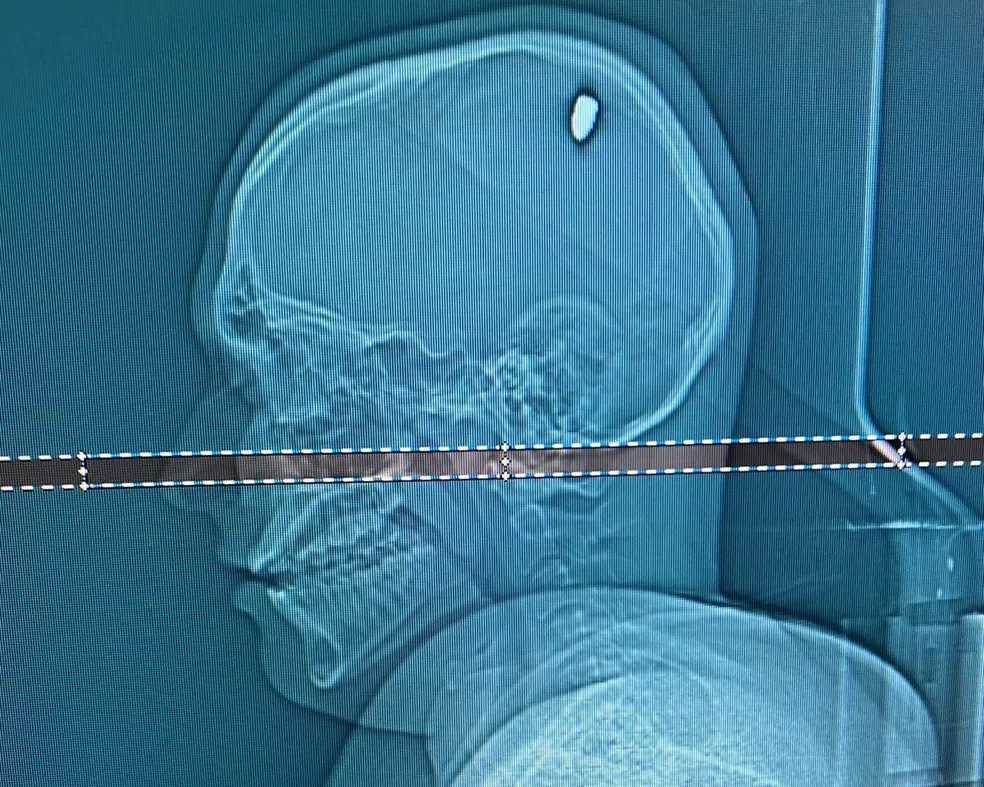

Um jovem de 24 anos foi socorrido em estado gravíssimo à emergência do Hospital Municipal de Ji-Paraná após atirar contra a própria cabeça durante a madrugada deste domingo, 15 de março de 2026, no bairro Novo Horizonte.

De acordo com informações preliminares, o rapaz teria efetuado um único disparo com um revólver, atingindo a própria cabeça em uma suposta tentativa de tirar a própria vida, enquanto estava em casa com familiares, pouco antes de todos irem dormir, no bairro Novo Horizonte, em Ji-Paraná (RO).

Segundo relatos, assim que deu entrada na unidade hospitalar, o jovem de 24 anos foi encaminhado em estado grave para o centro cirúrgico, devido à gravidade do ferimento causado pelo disparo na cabeça. A identidade da vítima não foi revelada até o momento, para preservação da família, que acompanha o caso de perto no hospital.